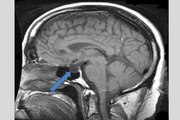

2015 Charlie Kaufman, David Thewlis, Jennifer Jason Leigh, Tom Noonan.\r<br>\r<br>Abnormal Psychology Video.\r<br>\r<br>In this clip we see a Capgras delusion patient, a condition presumably caused by impaired connections between the visual areas of the temporal lobe and the .\r<br>\r<br>A kid suffers from the mental disorder known as Fregoli Delusion. Everlast-I Get By RJD2-Cornbread, Eddie & Me Stevie Wonder-Superstition Everlast-What Its .